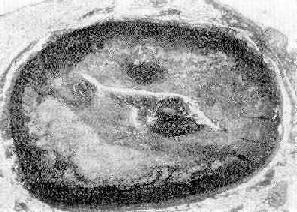

图8-28 冠状动脉粥样斑块并发血栓形成 图示左前降支粥样斑块,累及动脉壁四周,斑块底部粥样物中含大量胆固醇结晶;管腔被血栓阻塞(男性,50岁) 2.冠状动脉痉挛 多年来,学术界一直围绕着冠状动脉痉挛是否是缺血性心脏病的原因这一问题进行争论。有人研究心性急死例中发现,其冠状动脉血栓形成的发病率仅为30%,在发作后12小时内死亡的患者中也只占50%,故认为至少有相当部分病例是由于冠状动脉痉挛引起的。近年来,由于心血管造影技术的开展,已证实冠状动脉痉挛可引起心绞痛和心肌梗死。

图8-29示图8-28管腔内血栓的放大,主要为白色血栓(↑);右下为纤维素 3.炎症性冠状动脉狭窄冠状动脉的炎症可引起冠状动脉狭窄,甚至完全闭塞而造成缺血性心脏病,例如结节性多动脉炎、巨细胞性动脉炎、高安动脉炎、Wegener肉芽肿病等均可累及冠状动脉。此外,梅毒性主动脉炎亦可造成冠状动脉口狭窄,但都比较少见。